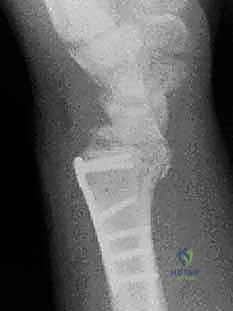

3. كسور الجزء الكردوسي الكردوسي (Ulnar Metaphyseal Fractures)

الجزء الكردوسي هو العنق أو المنطقة الانتقالية التي تربط رأس الزند بجسم العظم (Diaphysis).

هذه المنطقة تحتوي على عظم إسفنجي (Cancellous bone) وهي عرضة للكسور المفتتة (Comminuted fractures) خاصة عند كبار السن المصابين بهشاشة العظام، أو في حالات الحوادث عالية الطاقة. الكسر هنا يؤدي إلى قصر في طول عظم الزند، مما يغير من ميكانيكية توزيع الأحمال في المعصم ويسبب متلازمة انحشار الزند (Ulnar Impaction Syndrome).

توضيح لكسور الجزء الكردوسي الكردوسي

استخدام الأشعة السينية في التشخيص

1. الأشعة السينية (X-rays): بوضعيات متعددة (أمامية خلفية، وجانبية دقيقة). الوضعية الجانبية الحقيقية (True Lateral) حاسمة لاكتشاف أي خلع جزئي في المفصل (DRUJ).

ثانياً: العلاج الجراحي (Surgical Intervention)

4. الكسور المفتتة: في الجزء الكردوسي التي تؤدي إلى قصر عظم الزند.